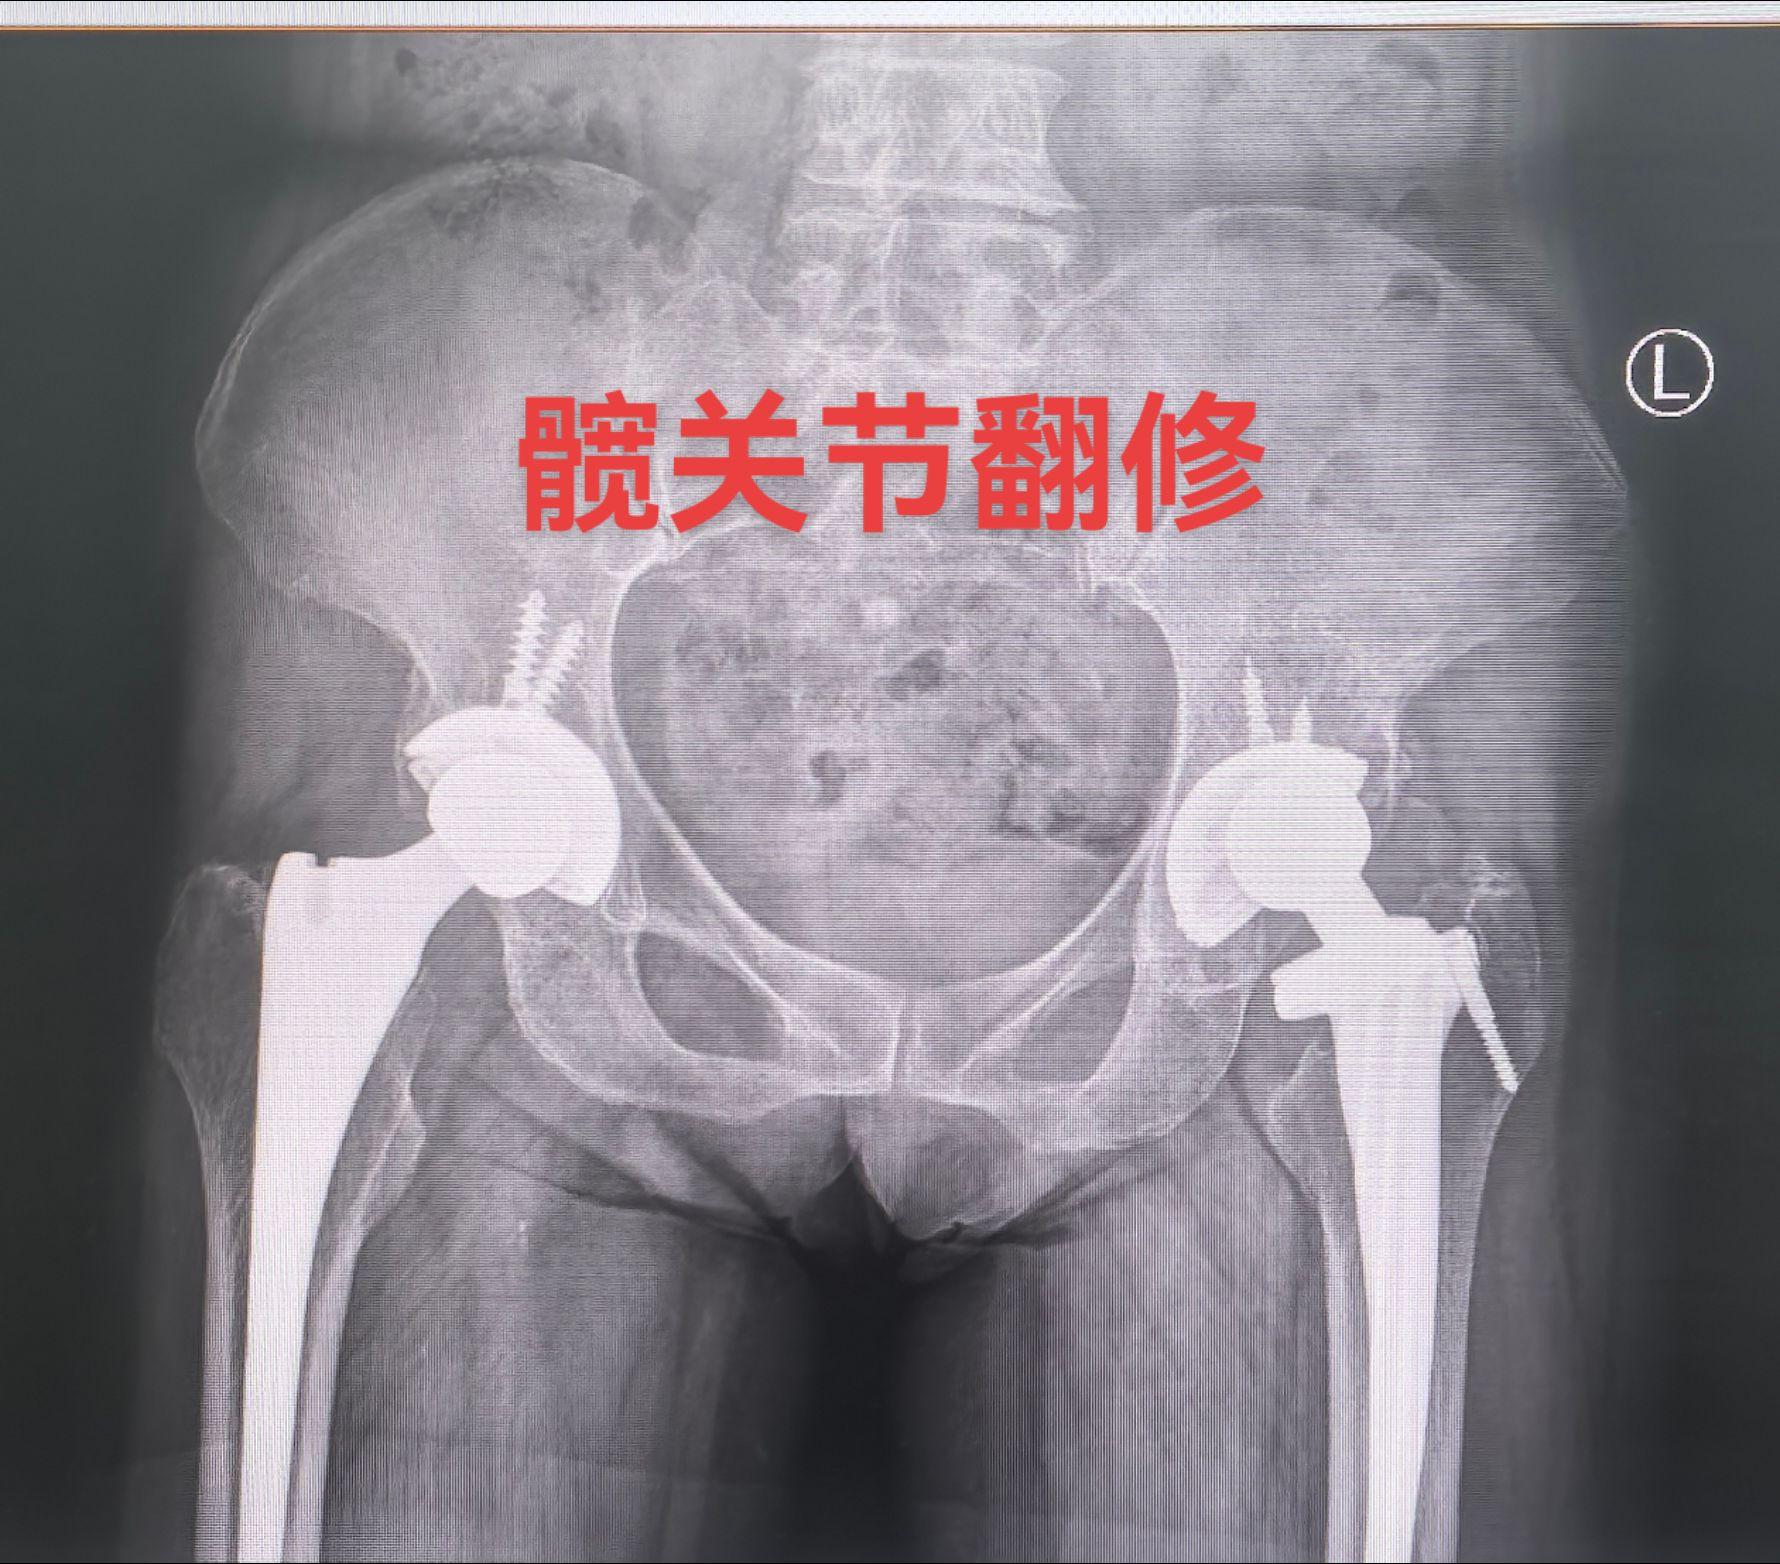

全髋关节翻修术。82岁老太太,THA后(14年)假体松动、骨溶解,全髋...